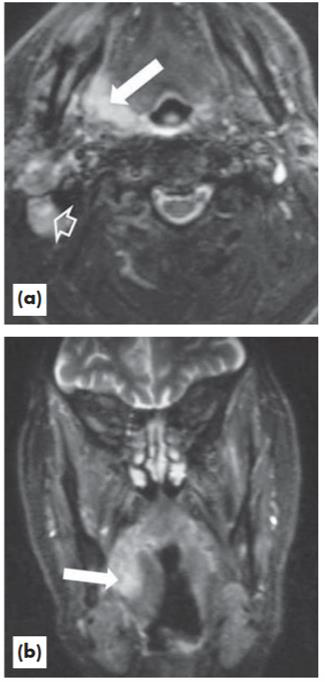

Com relação ao sítio da lesão apresentada na imagem (“a” plano axial; “b” plano coronal), bem como as estruturas identificadas e destacadas, assinale alternativa correta.